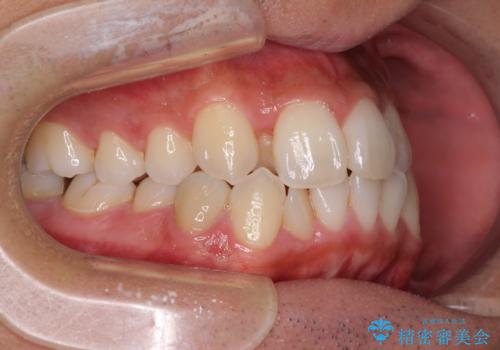

- 前歯のデコボコとクロスバイトを気にして来院された患者様です。

下顎の歯列弓に対して上顎歯列弓がやや小さく、側方の歯を中心にクロスバイトが見受けられました。

奥歯の咬み合わせは接触が少なく物足りないように見えますが、患者様としては十分に咬むことができるとのことでした。